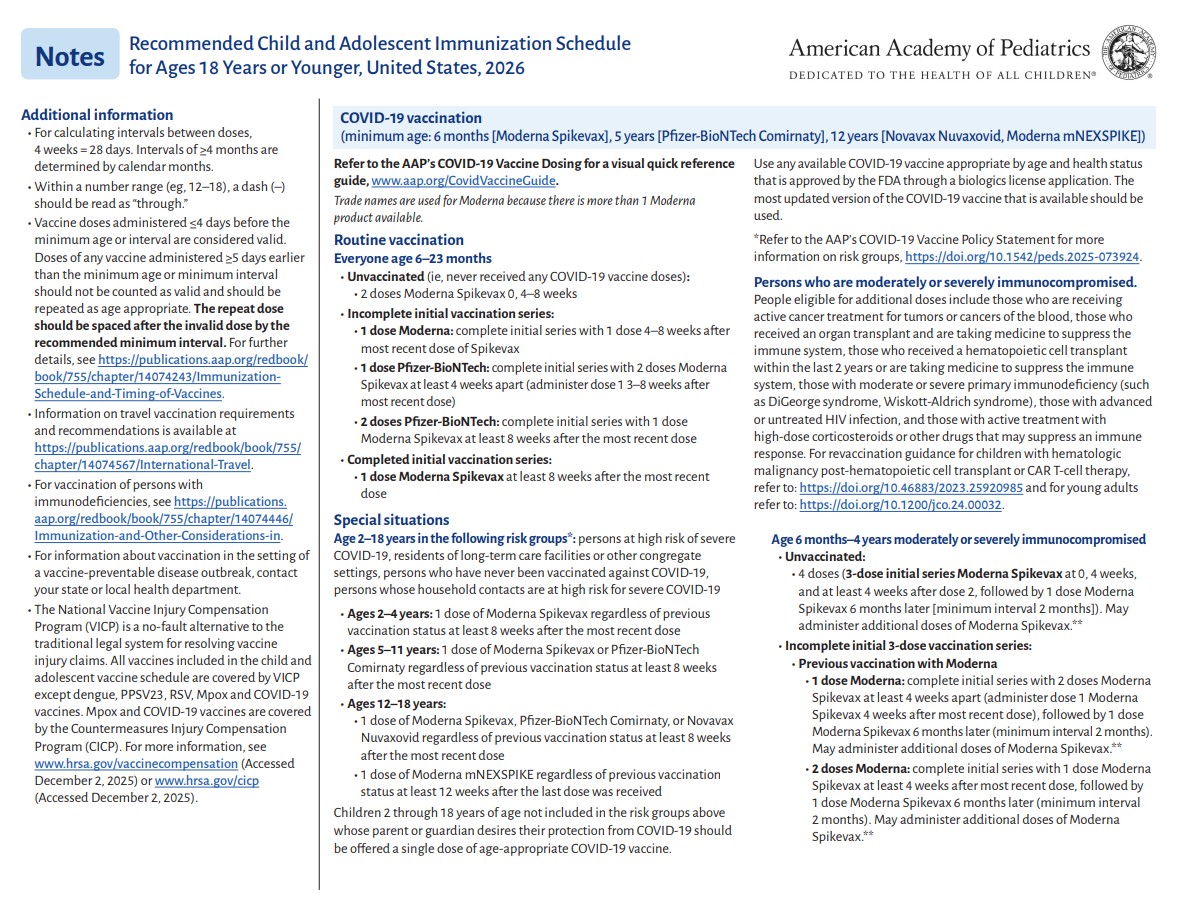

p 1